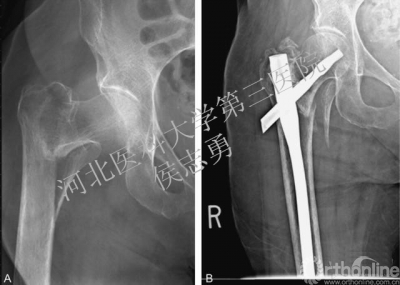

图1 A,右髋正位片显示AO分型31-A12型骨折;B,右髋正位片显示短款股骨近端髓内钉固定术后,骨折完全愈合。

图2 A,右髋正位片显示AO分型31-A21型骨折,后内侧有一个很大的骨折块;B,长款股骨近端髓内钉固定术后12个月时的右髋正位片,注意螺旋刀片向外移位。